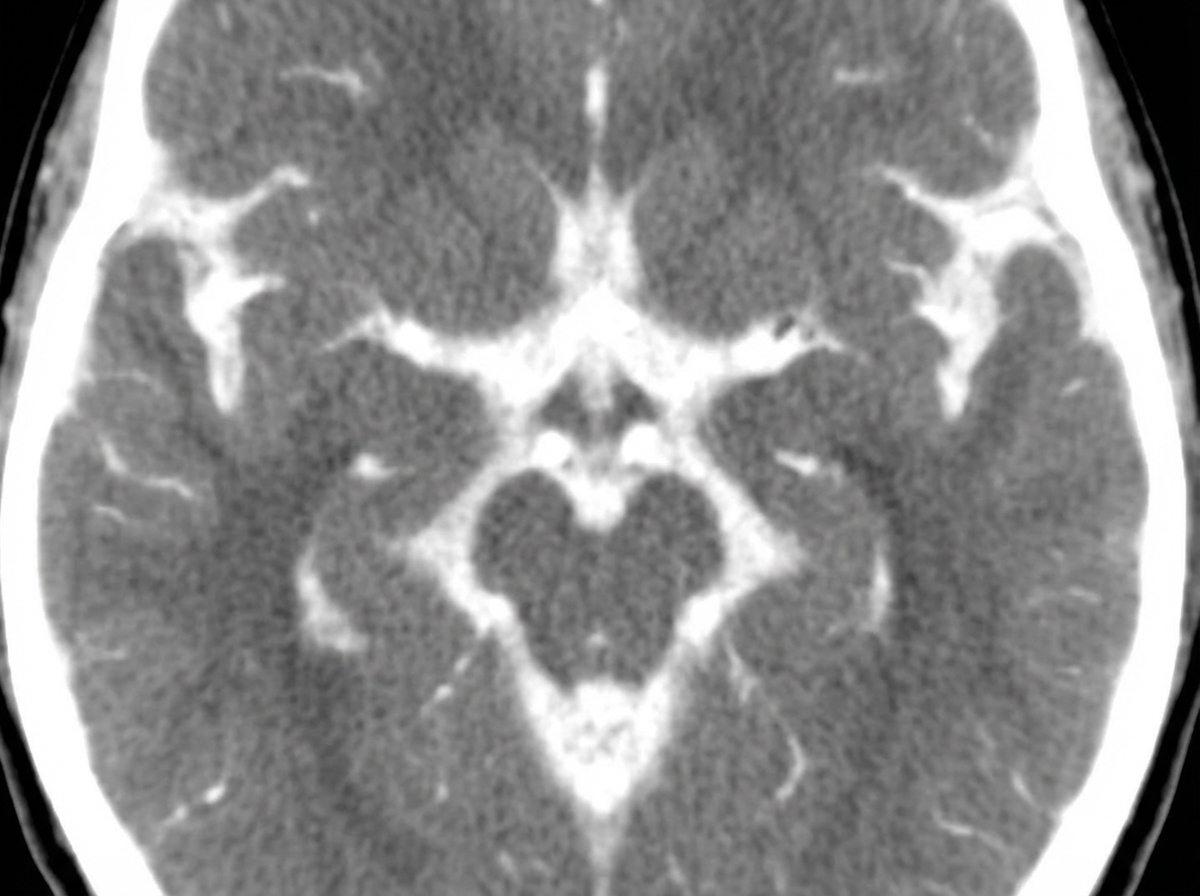

A 32-year-old woman presents with a severe headache and neck pain for the past 60 minutes. She says the headache was severe and onset suddenly like a ‘thunderclap’. She reports associated nausea, vomiting, neck pain, and stiffness. She denies any recent head trauma, loss of consciousness, visual disturbances, or focal neurologic deficits. Her past medical history is significant for hypertension, managed with hydrochlorothiazide. She denies any history of smoking, alcohol use, or recreational drug use. The vital signs include: temperature 37.0°C (98.6°F), blood pressure 165/95 mm Hg, pulse 92/min, and respiratory rate 15/min. On physical examination, there is mild nuchal rigidity noted with limited flexion at the neck. An ophthalmic examination of the retina shows mild papilledema. A noncontrast computed tomography (CT) scan of the head is performed and shown in the exhibit (see image). Which of the following is the next best step in the management of this patient?